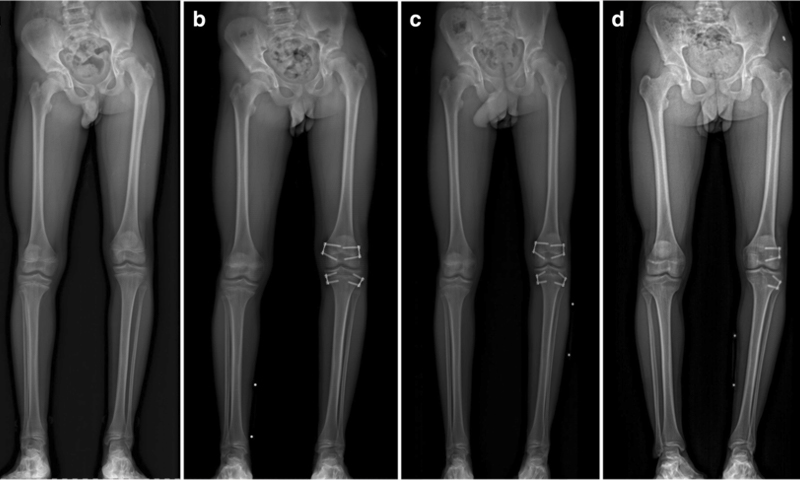

When it comes to bone and joint issues in children, seeking care from a specialist pediatric orthopedic surgeon is crucial for optimal treatment and long-term outcomes. Pediatric orthopedic surgeons have advanced training and expertise in addressing the unique needs of growing bones and joints. As children are still growing, their bodies response to injuries, infections, and deformities are different than a full grown person. In addition, the evaluation and treatment of a child is usually quite different than for an adult, even for the same problem.

• Has congenital orthopedic conditions like clubfoot or hip dysplasia.